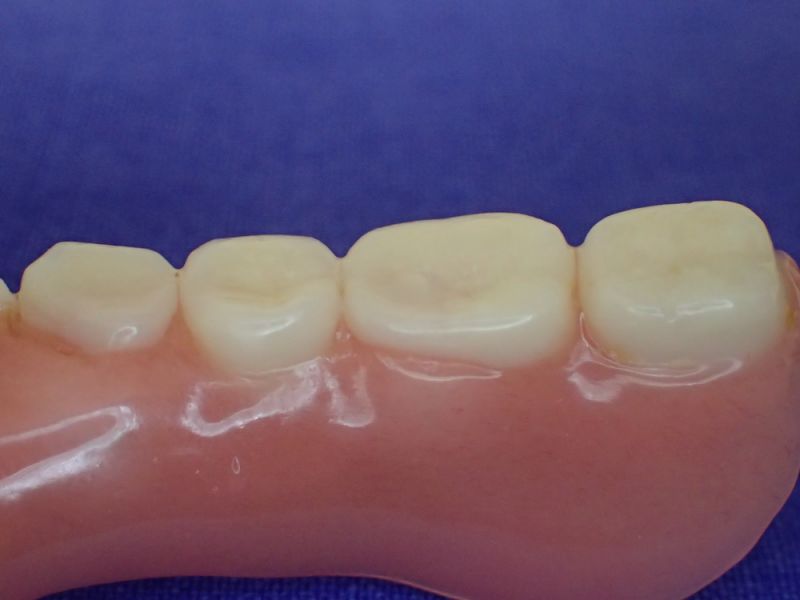

Nach inzwischen 12 jähriger Tragedauer wurden alle Kunststoffteile erneuert, das metallische Grundgeroüst der Arbeit erhalten und die Arbeit befindet sich in einem Zustand, der sich weitgehend an der Ersterstellung orientiert.

Bei derartigen Arbeiten ist es tatsächlich möglich grundlegende Konstruktionsmerkmale einer alten Arbeit zu übernehmen und Verschleißteile aus Kunststoff zu erneuern.